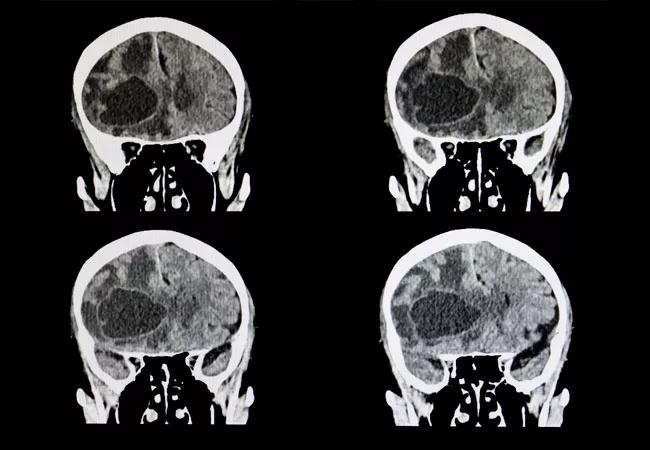

Phase 1 Study Supports Dose-Escalating Preoperative SRS for Large Brain Metastases

A research effort, led by Cleveland Clinic experts, demonstrated that preoperative stereotactic radiosurgery (SRS) with dose escalation followed by surgical resection for brain metastases larger than 2 cm led to local control that is similar to standard approaches (i.e., postoperative SRS or whole-brain radiation therapy), and with potentially fewer long-term side effects.

“Single session stereotactic radiosurgery alone for certain brain metastases (>2 cm in diameter) typically leads to suboptimal local control,” says Dr. Murphy. “Additionally, surgical resection alone also results in unreliable local control and perioperative radiation is needed. We initiated this prospective, phase 1 trial to determine the safety of preoperative SRS at escalating doses followed by surgical resection.”

This study included three radiosurgery dose cohorts based on maximum tumor diameter of the index lesion: 18 Gy for >2-3 cm, 15 Gy for >3-4 cm and 12 Gy >4-6 cm. Concurrent stereotactic radiosurgery alone to other smaller lesions was permitted using standard RTOG dosing.

This analysis included 35 patients with a median age of 63 years. The median interval between SRS and surgery was two days. Among enrolled patients, the most common histology was non-small cell lung cancer (57.1%), followed by breast cancer (14.3%).

Patients with a tumor size of >2-3 cm were enrolled up to the second dose level (21 Gy). The third dose level was reached for patients in the >3-4 cm and >4-6 cm cohorts (21 Gy and 18 Gy, respectively).

Study authors observed a total of three dose limiting toxicities. Two occurred in the >3-4 cm cohort (grade 3 wound dehiscence and grade 3 wound infection) and one in the >4-6 cm group (grade 4 hematoma).

“We determined that the maximum tolerable dose was 18 Gy (2nd dose level) for the >3-4 cm cohort, and 18 Gy (3rd dose level) for the >4-6 cm group,” says Dr. Murphy, while discussing their key findings.

“At two years, the rate of leptomeningeal disease was 0%,” she reports. “This suggests a significant benefit over post-operative radiosurgery, which demonstrates a higher rate of leptomeningeal disease. Additionally, we observed good local control after long-term follow up. At a median median follow-up of 64 months, the six- and 12-month local control rates were 88.8% and 79.1%, respectively.”

Dr. Murphy and her colleagues also found that preoperative stereotactic radiosurgery with dose escalation followed by surgical resection led to six- and 12-month distant brain control of 63.1% and 55.3%, respectively. Overall survival at six and 12 months was 82.9% and 59.0%.